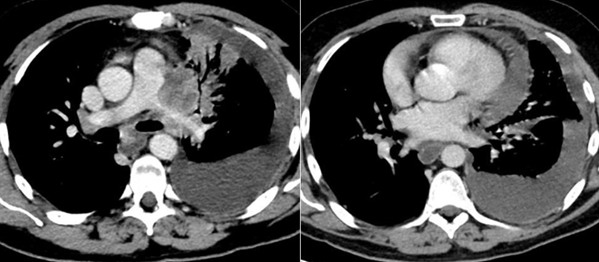

A

Masa pulmonar izquierda sin afectación broncovascular. Colección pleural y pericárdica.

B

Masa pulmonar izquierda sin afectación broncovascular. Colección pleural sin afectación pericárdica.